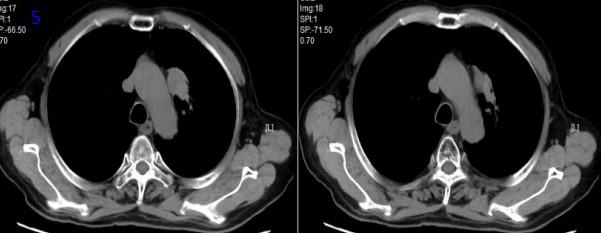

2022年3月15日再程放療后5個月復(fù)查胸部CT可見腫瘤較前縮?。▓D7),RECIST評價PR。

圖7再程放療后胸部CT